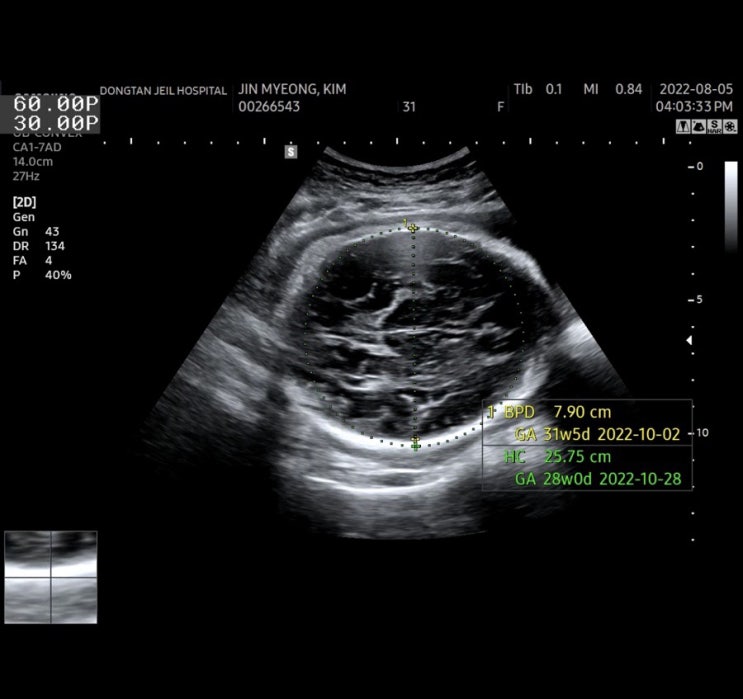

36주 6일차 동탄제일병원 검진

36주 6일차에 검진 다녀왔어요 혈압이랑 몸무게측정하고 소변검사도 함 * 31주부터는 소변스틱검사도 매번 ...